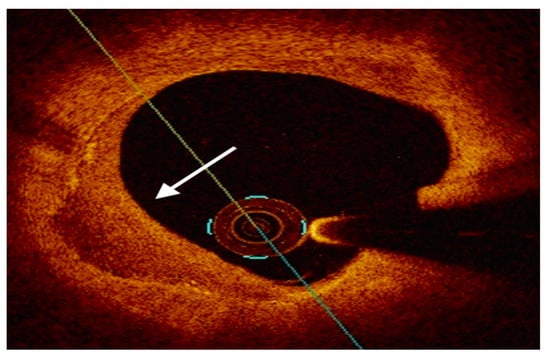

Furthermore, OCT is the gold standard tool to assess the mechanisms of atherosclerotic plaque destabilization. PR is recognizable as a discontinuity in the FC associated with a cavity inside a lipid rich plaque (LRP) with or without thrombotic material; OCT-derived PE is an exclusion diagnosis, which relies on the recognition of intact fibrous cap accompanied by an overlying white thrombus or irregular surface [42][65]. Finally, calcified culprit plaque was characterized by Sugiyama et al. into three distinct patterns with different OCT appearance and natural history: eruptive calcified nodules, calcified protrusions and a superficial calcific sheet [47][76]. In this context, OCT was observed to overcome IVUS for investigating the underlying mechanism of ACS [48][77] (Figure 4).

Figure 4. Examples of OCT-derived mechanisms of plaque destabilization. (A) Example of a ruptured plaque, characterized by the evidence of a cavity with a clear discontinuity of the fibrous cap ((A), white arrow). (B) Example of a definite eroded plaque, characterized by a luminal thrombus ((B), white arrow) overlying a plaque without evidence of fibrous cap disruption. (C) Example of a calcific nodule ((C), white arrow), depicted as single of multiple regions of calcium that protrude into the lumen with fibrous cap disruption.